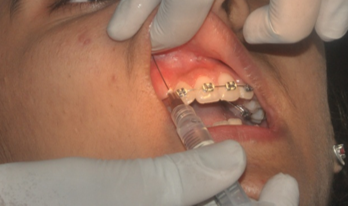

Topical anaesthesia followed by local infiltration (Septodont, France) with 2 % Lignocaine HCL with adrenaline 1:100000 was used before performing intervention as shown in ([Figure 2])